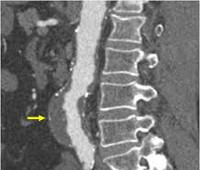

КТ аорты выполняют при воспалительных, деструктивных, атеросклеротических, опухолевых поражениях. Процедура показана при подозрении на аневризматическое расширение, расслоение аорты, тромбоз, эмболию, перегиб, сужение просвета из-за стенозирования или окклюзии в результате рубцово-спаечного процесса. КТ-аортографию осуществляют при предоперационном обследовании пациентов для планирования объёма хирургического вмешательства на магистральном артериальном стволе. Методику используют для контроля хода операции, наблюдения в послеоперационном периоде, а также для оценки состояния стента или протеза.

КТ брюшной аорты назначают с целью получения трёхмерного изображения сосудов брюшной полости: аорты, чревного ствола, почечных и нижней брыжеечных артерий, селезеночной артерии с целью визуальной оценки строения и состояния сосудистой системы. КТ брюшного отдела аорты информативна при опухолевых процессах с целью выявления брыжеечных и парааортальных метастазов в лимфоузлы и сосуды или при аномалиях развития аорты и её ветвей (фибромускулярная дисплазия почечных артерий, мальформации ).

Показанием к КТ грудной аорты является коарктация аорты, открытый проток между аортой и лёгочной артерией, атеросклероз сосудов, стеноз устья аорты. Сканирование производится для выявления аортита (туберкулёзного или сифилитического), опухолевых процессов в стенках сосудов, в том числе при прорастании новообразований из органов средостения.